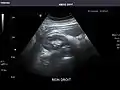

Abdominal Ultrasound (Full Exam)

STRUCTURED REPORT

(Technique: Transabdominal ultrasonography; Device: Toshiba Aplio XG)

Liver: Diffusely homogeneous and normal in echogenicity. No focal mass or contour nodularity. No intrahepatic biliary ductal dilatation.

Portal Vein: Patent main portal vein.

Gallbladder: No stones, wall thickening, or pericholecystic fluid.

Common Bile Duct: Nondilated measuring 1.3 mm at the level of the porta hepatis.

Pancreas: Visualized portions unremarkable.

Spleen: Normal in size.

Kidneys: Right and left kidneys measure 11.5 cm and 12 cm in length respectively. No hydronephrosis. Small left lower pole kidney cyst.

Ascites: None.

Aorta: Visualized portions normal in caliber, 16 x 15 mm.

IVC: Normal.

IMPRESSION:

Normal abdominal ultrasound.